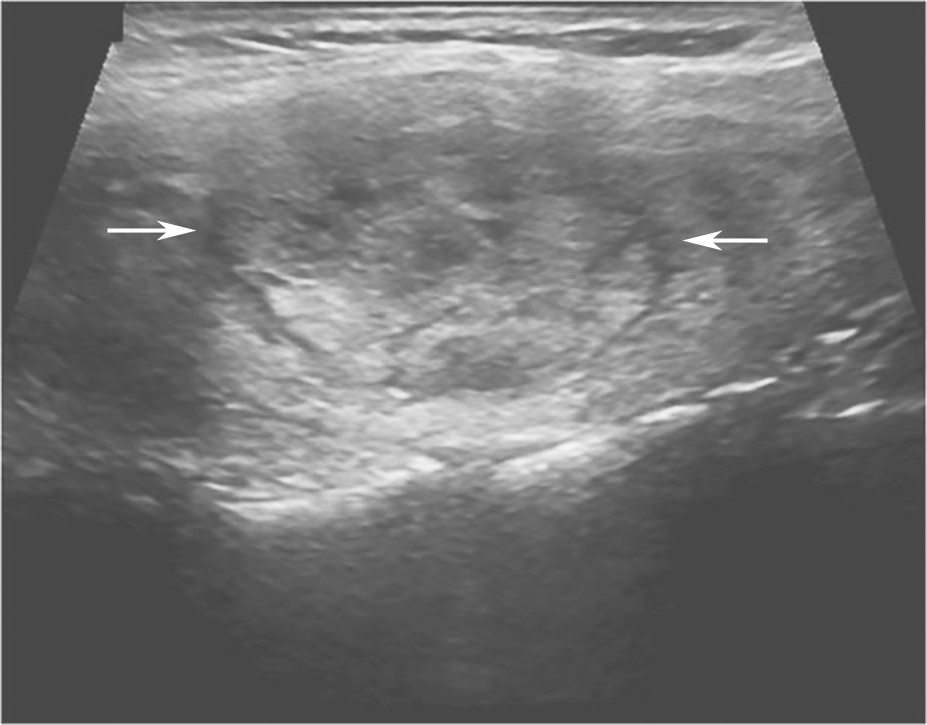

(十三)甲状腺淋巴瘤

甲状腺淋巴瘤超声表现多样,可大致分为结节型、弥漫型、混合型。结节型多见,多为极低回声,边界清楚,后方回声增强,呈“假囊征”,钙化或液化很少出现,有时低回声可呈“蜂窝状”改变;弥漫型表现为双侧叶肿大,内部为极低回声,肿瘤和甲状腺组织的分界无法识别;混合型表现为多个极低回声病灶,不均分布在腺体内(图16)。上述各型共同特点为病变呈极低回声,后方回声增强,病灶内部血流信号丰富(图17,图18)。

.jpg)

图16颈部正中偏右横切面:甲状腺右叶极低回声,占据整个腺体(箭头所示)